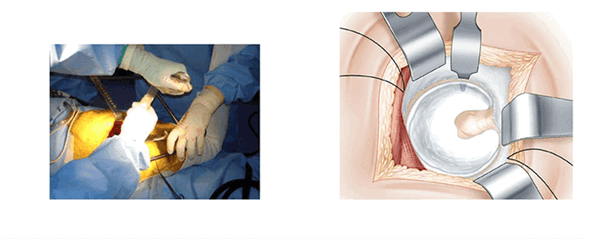

Схема выполнения модифицированного бокового доступа к тазобедренному суставу пациентки Л.: на средней ягодичной мышце намечены три разреза для формирования лоскута (интраоперационное фото)

Модифицированный боковой доступ к тазобедренному суставу включает следующие этапы: разрез кожи в проекции большого вертела, рассечение широкой фасции бедра, выполнение трёх разрезов. Первый разрез от проксимальной точки по ходу мышечных волокон средней ягодичной мышцы в передне-верхнем направлении длиной 3 см, второй разрез от точки на границе между средней и дистальной третью большого вертела в направлении кпереди, отступив от центральной линии 1 см, длиной 3 см, третий разрез производят, соединяя начальные точки первого и второго разрезов между собой в виде дуги, направленной выпуклой стороной кпереди (рисунок), отсекают среднюю ягодичную мышцу от передней поверхности большого вертела в пределах выполненных разрезов, полученный лоскут средней ягодичной мышцы смещают кпереди и фиксируют при помощи инструментов. Затем вывихивают головку бедренной кости и выполняют эндопротезирование тазобедренного сустава. После основного этапа смещённый кпереди сформированный мышечно-сухожильный лоскут укладывают на своё место и фиксируют при помощи швов [4].